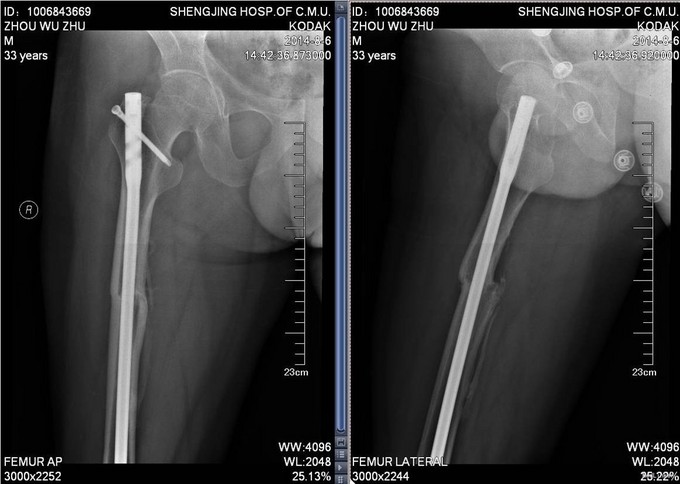

患者2012年8月发生车祸,致右股骨及左胫骨骨折,后于我院行右股骨骨折闭合复位内固定术,左胫骨骨折闭合复位内固定术,手术顺利,安返病房,术后康复锻炼,定期复查,近期复出X线,提示骨折愈合良好,今日门诊以“右股骨骨折,左胫骨骨折术后”为主要诊断收入我科

患者步入病房,神志清,右大腿压痛叩击痛(—),左小腿压痛叩击痛(—)。双下肢等长。双下肢感觉运动均正常。

入院后完善检查,查无手术禁忌症后右股骨干骨折术后内固定物取出术,左胫骨骨折术后内固定物出去术,术后第二天自动退院。